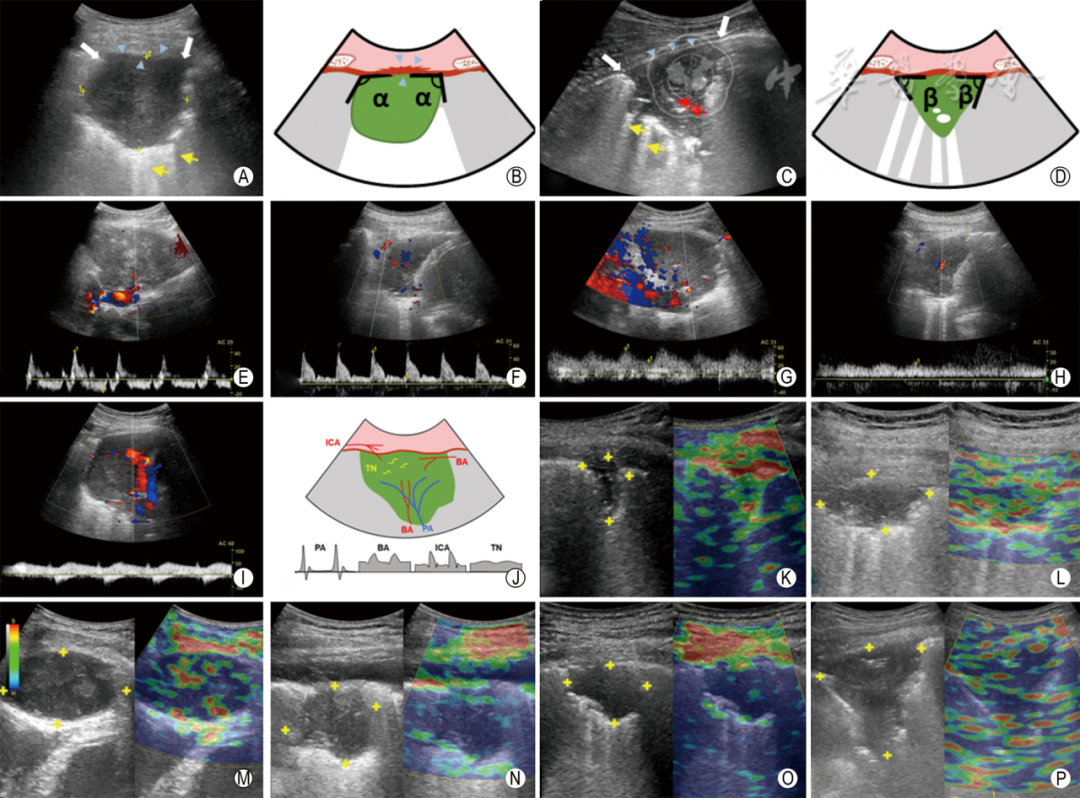

(3)术前评估病灶内血供及周围血管情况,避免损伤粗大血管、肋间动脉,穿刺路径尽量避开实变肺组织,减少穿刺次数(图7 A~D);

同轴定位针怎么使用专家共识丨超声引导经皮肺穿刺活检中国专家共识(2025版)_https://www.jmylbn.com_新闻资讯_第13张

图7  超声引导经皮肺穿刺活检常见并发症 A:常规超声图像显示病灶内存在支气管充气征和粗大血管(图中蓝色血流信号); B:活检时切割针损伤血管,导致咯血(红色箭头所示为穿刺针); C:CDFI显示病灶大部分区域血供丰富(图中红色、蓝色血流信号区),仅一侧边缘血流信号较少(红色箭头所指); D:在无明显血管处进针穿刺活检,避免出血并发症(红色箭头所示为穿刺针); E:肋间动脉起始于脊柱旁,走行于肋骨上缘,向前胸走行过程中逐渐靠近上位肋骨下缘,但随年龄增长,肋间动脉走行扭曲明显。 F~K图为一出血并发症病例(男,62岁)。 F:常规超声示病灶周边及内部未见明显血流信号; G:CEUS示病灶不均匀等增强; H:穿刺活检术中,针道清晰,操作顺利(红色箭头所示为穿刺针); I:术后常规超声示胸腔内巨大凝血块(黄色十字所示); J:CT示右侧胸腔积血(红色箭头所示); K:血管介入发现肋间动脉多支破裂,给予封堵治疗。 L~N图为一气胸并发症病例(女,70岁)。 L:超声引导胸膜下肺病灶穿刺活检时发生气胸(红色箭头所示为穿刺针); M:通过同轴定位针抽气,病灶逐渐显示(红色箭头所示为同轴定位针); N:抽气20 ml后,病灶完全显示(红色箭头所示为同轴定位针)。 O~Q图为一气胸并发症病例(女,68岁)。 O:超声引导胸膜下肺病灶穿刺活检时发生气胸(红色箭头所示为穿刺针); P:穿刺时并发气胸,病灶受气体遮挡无法显示; Q:静卧、吸氧20 min后,气体吸收,病灶重新显示(黄色十字所示)。 R:空气进入血液循环的机制:穿刺针刺破肺静脉后拔出针芯,空气即可进入肺静脉;穿刺针穿破气道且同时穿破邻近肺静脉,形成气道-肺静脉瘘,空气可经瘘道进入肺静脉; S:胸膜下肺病灶,内弥漫分布支气管充气征,避开支气管穿刺活检,避免空气栓塞并发症的发生

(4)肋间动脉自肋脊交界区起始,一般沿肋骨下缘走行,但也存在个体差异和解剖变异,特别是随着年龄增大,肋间动脉的迂曲度增加无法被肋骨完全遮挡,穿刺时更易损伤。穿刺前可应用高频探头观察胸壁血管,避免损伤(图7 E);

(6)中-大量血胸应尽早发现,可行置管引流联合止血药物治疗,并及时明确出血来源。病情危重时,救治措施同咯血(图7 E~K)。

(1)术中少量气胸(肺压缩<30%)无需特殊处理,也可使用注射器抽气后继续操作(图7 L~N);

(2)稳定的闭合性气胸无需特殊治疗,注意观察病情变化,必要时吸氧、休息(图7 O~Q);